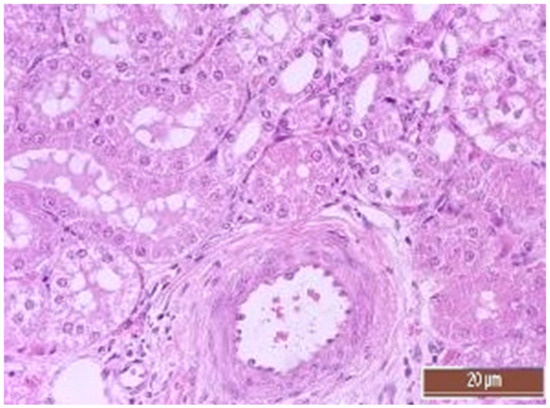

3.4. Pathology of Kidneys